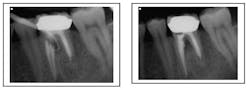

Some iatrogenic errors, such as canal transportation, ledges that inhibit patency, zipping of the apex, overfills, and perforation are all iatrogenic errors that may be best handled with a combined nonsurgical approach followed by a surgical approach to retreatment. In fact, retreating a case before performing a surgery improves clinical outcomes. (Wang, 2004) Surgery provides the surgeon the best visible information about the canal orientation and location to help with the resection and retrofill. Iatrogenic errors can be removed via root end resection and the remaining root tip can be retrofilled. Thus the entire intracanal infection has been addressed both orthograde and retrograde.

Case corrected with retreatment and root resection surgery (overfill)